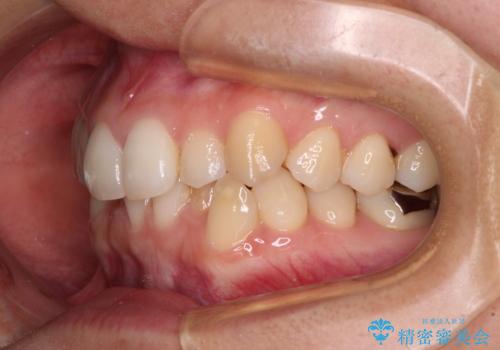

- 上下のクロスバイトと前歯のデコボコを気にして来院された患者様です。

インビザラインを用い、IPR(歯と歯の間を削る)と歯列全体を拡大させることで、歯並びを整えていくこととしました。

下の歯が隠れてしまうほどでしたが、深い咬み合わせも改善され、顎への負担も軽減されました。